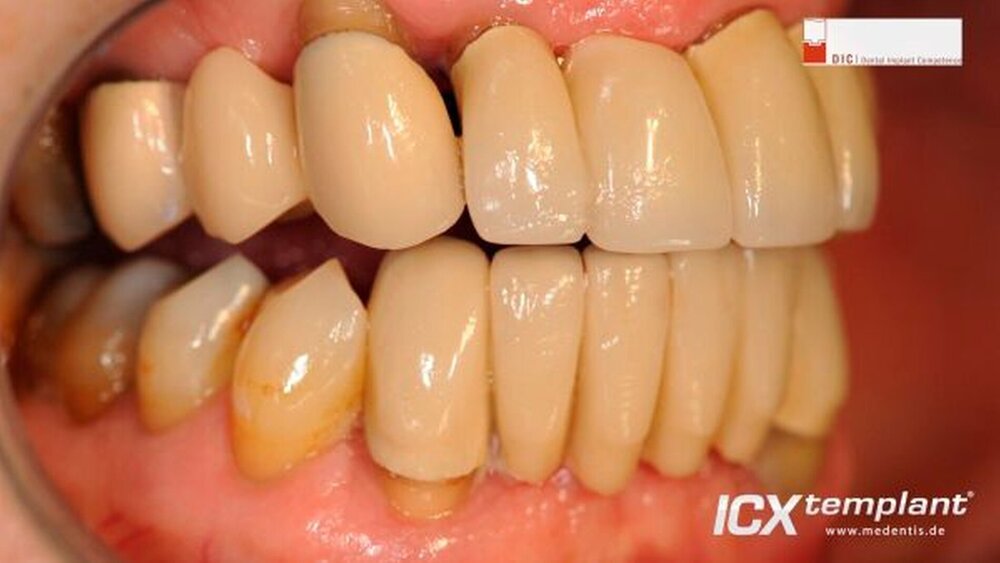

Implantation im zahnlosen Ober- und Unterkiefer

Die Operation wurde durchgeführt von Dr. Dr. Steffen Hohl (Buxtehude), Facharzt für Mund-, Kiefer- und plastische Gesichtschirurgie. Schwerpunkte: Implantologie, Oralchirurgie, Parodontologie, moderne 3D Verfahren, DIC / Dental Implant Competence.